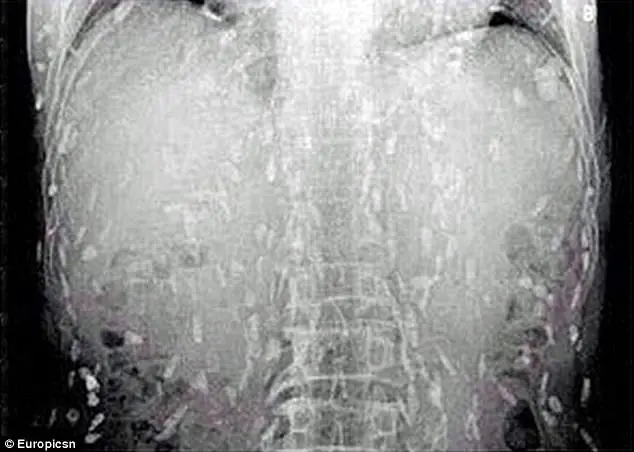

A quanto pare è stato il pesce crudo mangiato al ristorante a causare tutti i problemi al protagonista di questa disavventura. Una volta mangiate le prelibatezze giapponesi, il corpo di quest'uomo cinese è stato invaso da vermi solitari ed è stato immediatamente ricoverato al Guangzhou No. 8 People's Hospital nella provincia cinese di Guangdong. Le uova della tenia possono causare la cisticercosi, quando i vermi adulti penetrano nel sangue umano